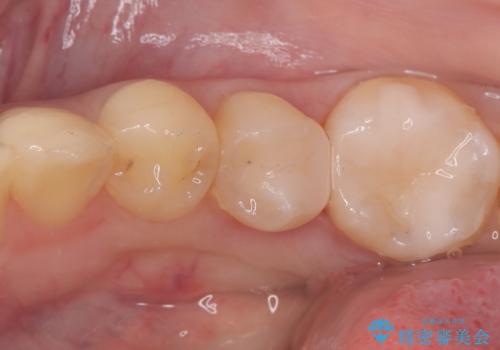

銀歯を外し、インプラントを入れたい